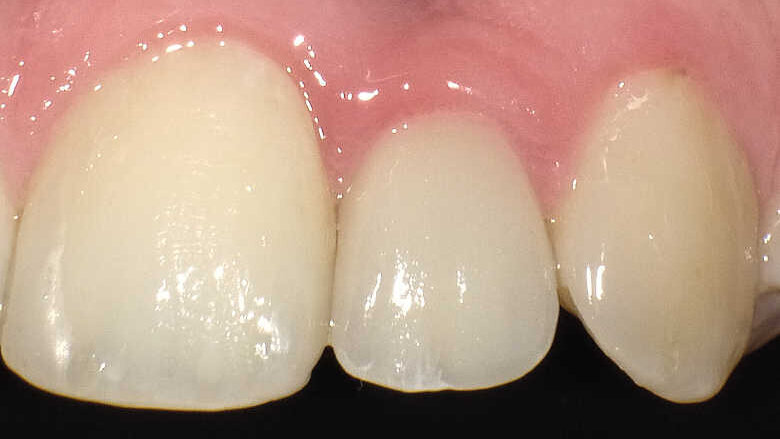

Fig. 9 : Contrôle intraoral de la couronne et du tissu mou périphérique après trois ans. À noter : la stabilité des papilles, soutenues par l’os formé sur l’épaulement incliné.

L’implant a été mis en place au moyen d’un instrument spécial pour l’insertion d’implant, qui permet au praticien de pousser l’implant fermement, en appliquant une pression précise dans l’ostéotomie (Fig. 5). La dernière étape a consisté à introduire complètement l’implant au moyen du maillet, et de l’instrument d’insertion fixé à la poignée de serrage droite. L’implant étroit était dès lors bien positionné entre les deux racines (Fig. 6). L’implant de 8 mm de long et de Ø 3 mm a été inséré par l’application d’une pression dans l’ostéotomie, et l’utilisation du maillet et de l’instrument d’insertion à 3 mm sous le niveau de l’os crestal (Fig. 7). La seconde phase du traitement a été réalisée après six mois de cicatrisation et a consisté à désenfouir l’implant. Un pilier ayant un corps de Ø 2 mm et une base hémisphérique de Ø 4 mm a été choisi pour connecter les couronnes provisoires à l’implant. Il est important de veiller à la bonne cicatrisation du tissu mou autour du contour coronaire adéquat, et celle-ci peut être obtenue par une modification du profil d’émergence de la couronne provisoire jusqu’à la formation des papilles. Après la cicatrisation complète du tissu mou, la dernière empreinte a été prise et la couronne définitive a été scellée sur le pilier en titane (Figs. 8 et 9).